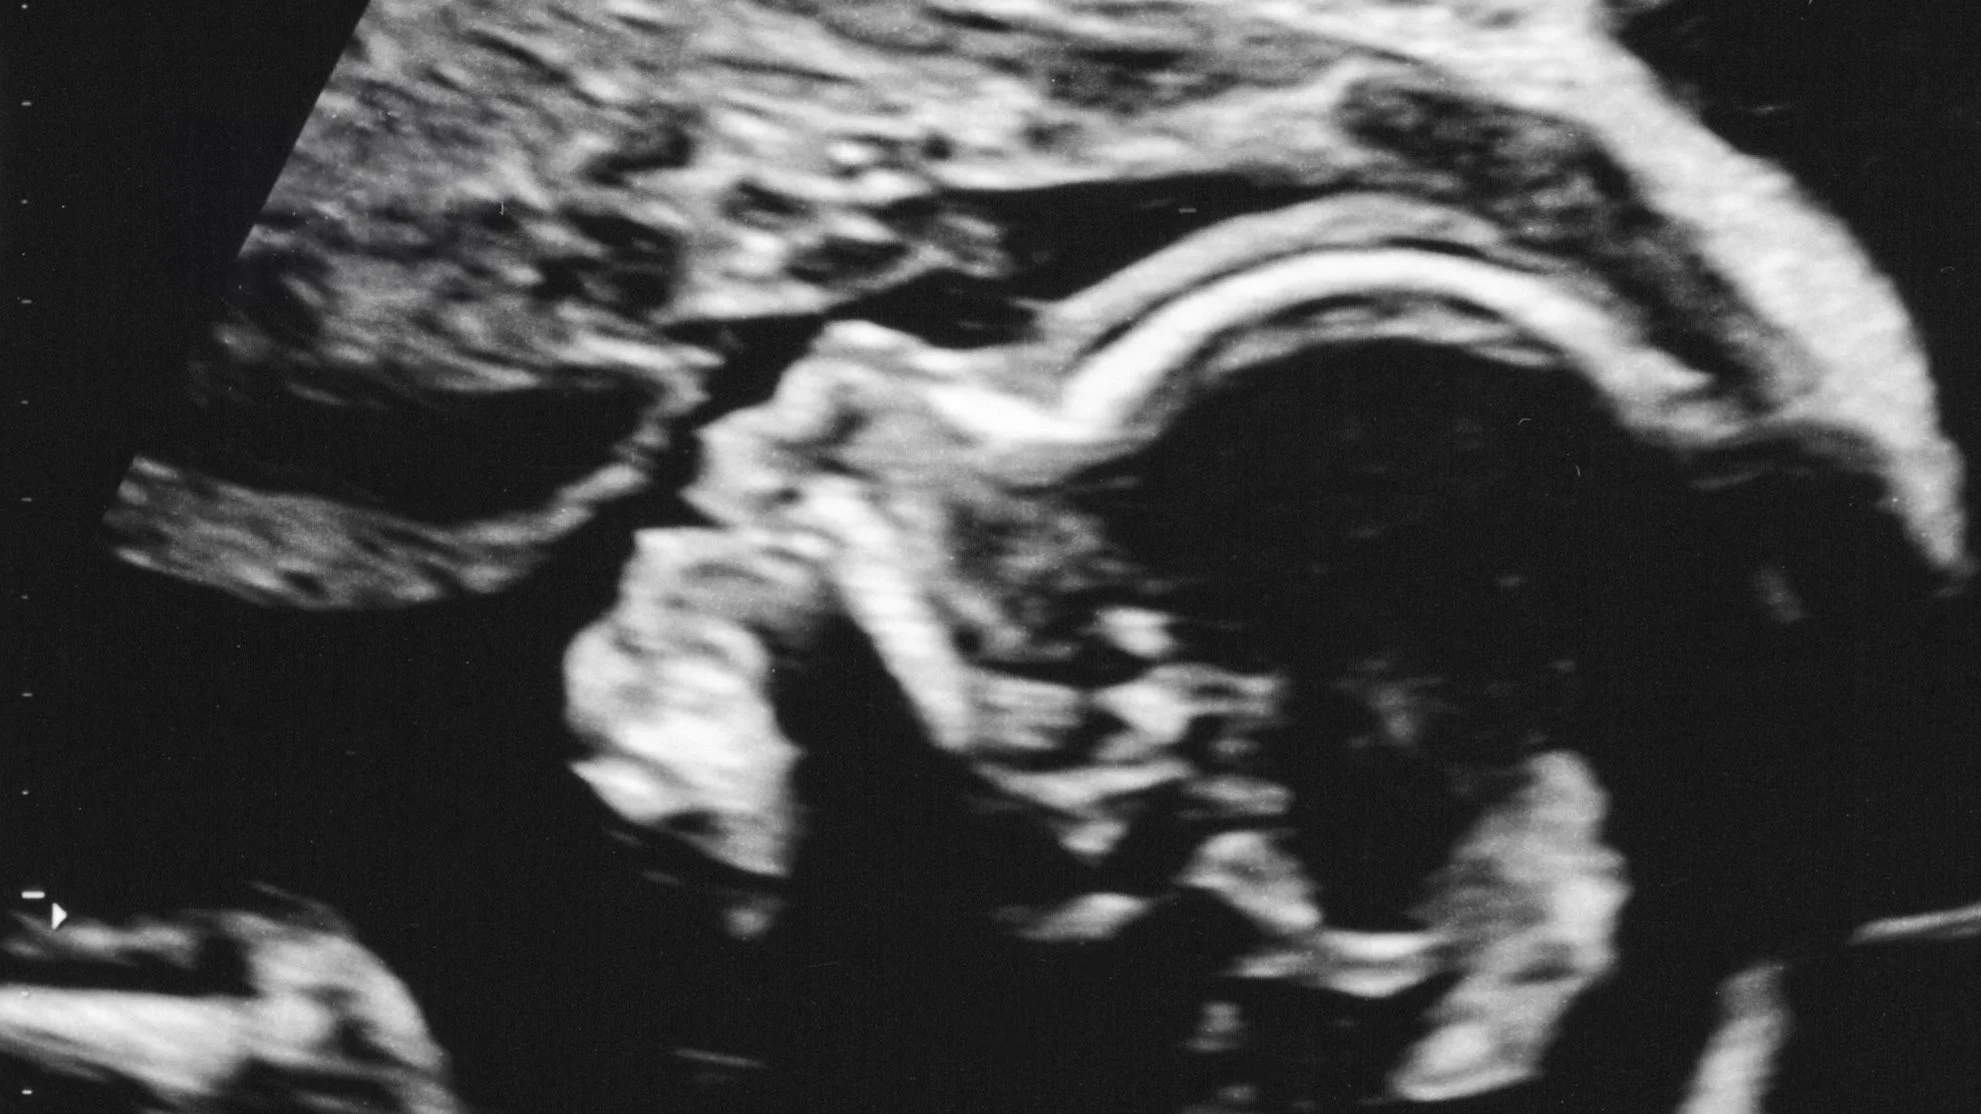

Thank you for celebrating baby Eleanor with us!